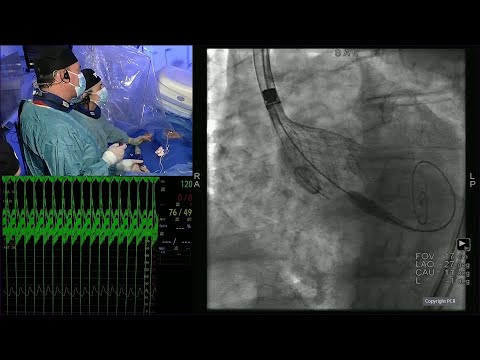

Maintaining selective coronary access after TAVI and re-do TAVI procedures - PCR London Valves 2022